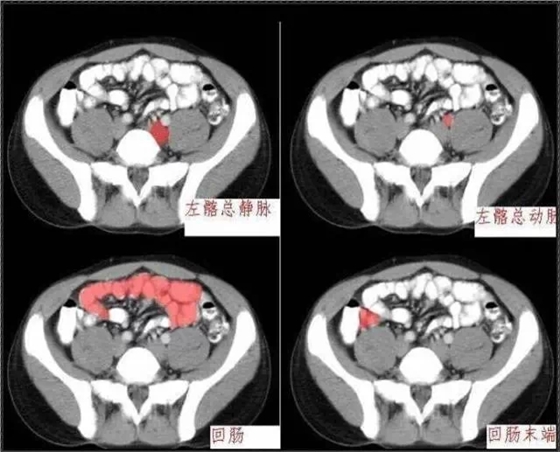

640.webp (1).jpg